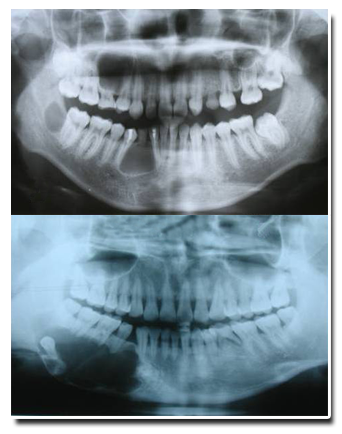

好发年龄,10-29岁,40-50岁,男多于女,多累及下颌骨,特别是磨牙及升支部,上颌第一磨牙,单发或多发,多发者可伴痣样基底细胞癌综合征 特殊的生长方式,沿颌骨前后方向生长,多数病人无明显症状,较大时颌骨膨胀,继发感染时出现疼痛、瘘管形成,X线表现单房或多房性透光区,边缘有扇形切迹,类似成釉细胞瘤、含牙囊肿。